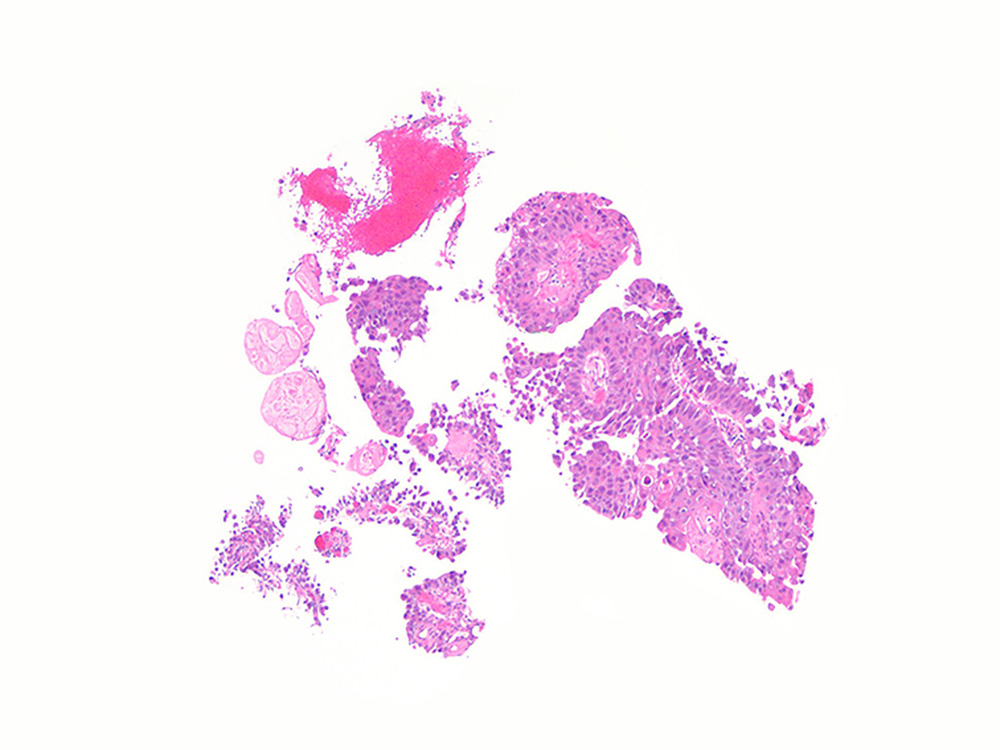

Bladder Papillary Lesions

Case ID: 273